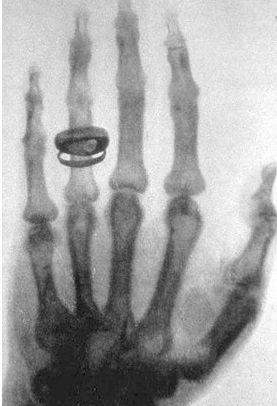

한의사 X-ray 사용에 75.8% 찬성

지난 2017년 한국사회여론연구소(KSOI)가 전국 성인남녀 1000명을 대상으로 실시한 ‘한방병의원 이용 및 현대의료기기 사용에 대한 인식조사’에 따르면, ‘한의병의원에서 한의사가 X-ray 및 초음파기기와 같은 현대의료기기를 사용하는 것에 대해 찬성하느냐 아니면 반대하느냐’를 묻는 질문에 ‘찬성한다’가 75.8%, ‘반대한다’가 19.0%로 집계된 바 있다.

이는 ‘방사선 발생장치 안전관리 책임자에 한의사를 포함하는 법적 근거를 마련해야 한다’는 찬성 여론이 81.0%에 이르고, ‘한의사의 초음파영상진단장치 진료 활용을 위한 법적 근거를 마련해야 한다’는 여론 또한 83.5%에 이르는 국민의 요구와 정면 배치된다.